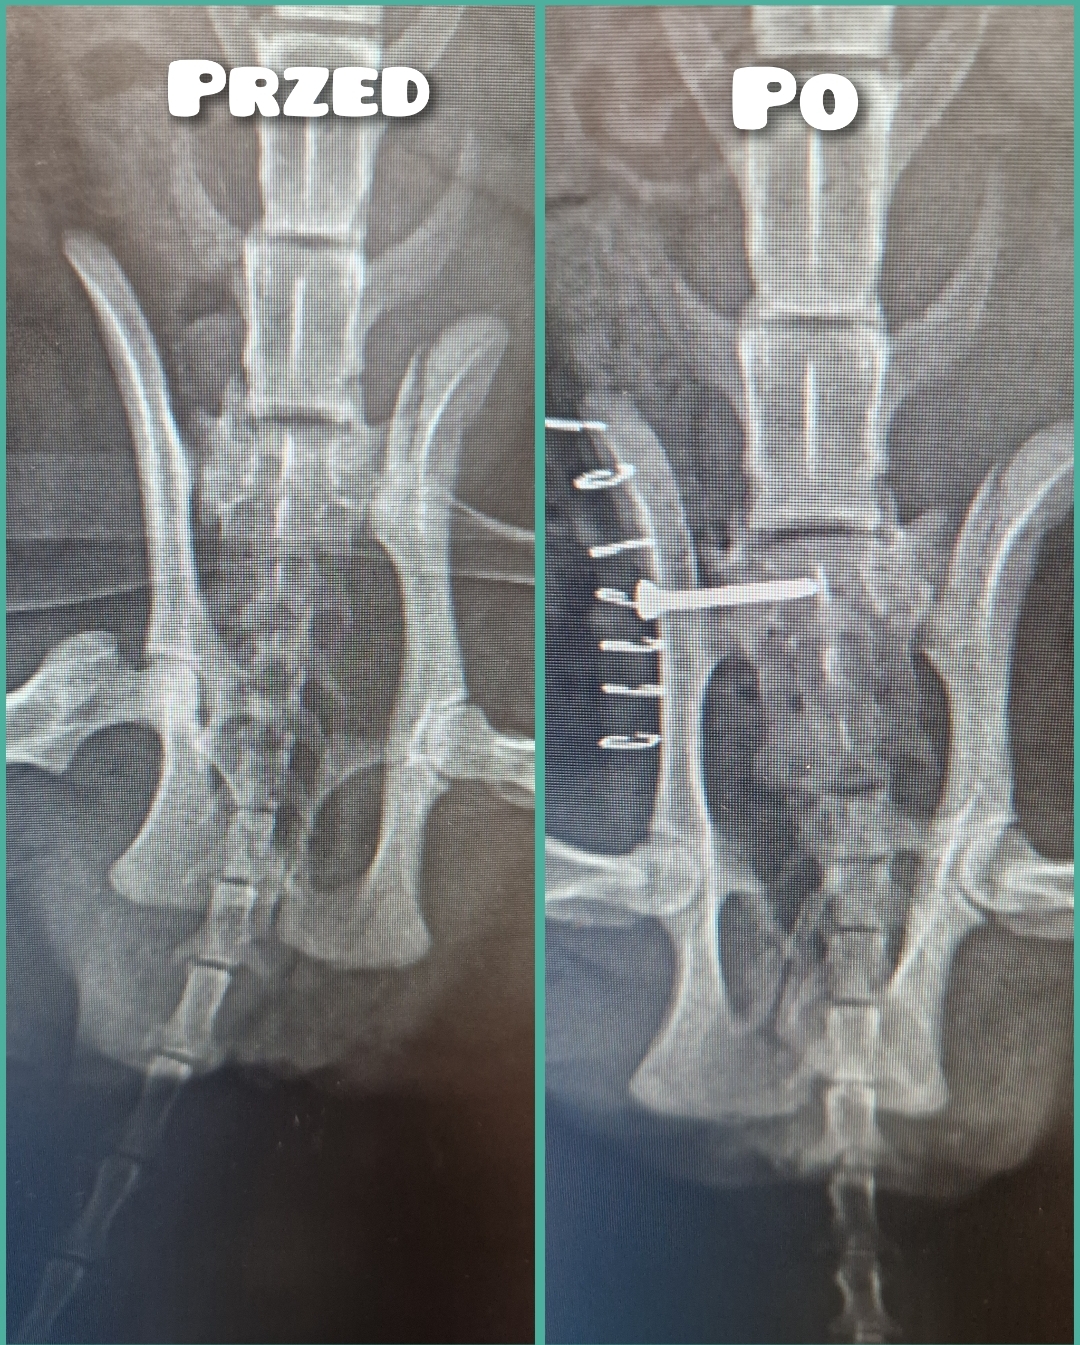

Jest szansa na uratowanie Bajki, ma złamaną prawą tylną łapką i pogruchotaną w kilku miejscach miednicę. Niestety - nasze możliwości finansowe się wyczerpały, życie dość mocno sie ze mną obeszło w ostatnich latach i nie mam generalnie nic. Dziś wydaliśmy wszystkie skromne oszczędności, żeby opłacić leczenie Bajki do tej pory.

Kochani, dzięki Waszym wielkim sercom Bajka dziś pomyślnie przeszła operację - DZIĘKUJEMY ????♥️???? Wielkie brawa dla lekarzy z lecznicy Cztery Łapy w Jeleniej Górze ! Koszt operacji wyniósł 3260 PLN plus każdorazowa wizyta kontrolna 30 PLN plus koszty dodatkowe za miesiąc, tj. wyjęcie śrub, leki, rehabilitacja. Dziś zapłaciłem 3000 PLN, załączam rachunek. Następne załączę przy kolejnych opłatach. Bajka wysyła miaubuźki (. ❛ ᴗ ❛.)